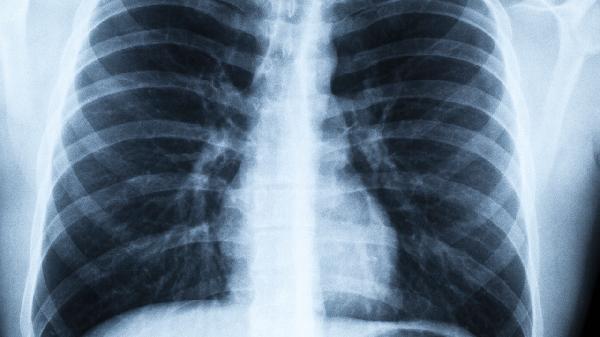

需要特别提醒的是,常规胸片检查对早期肺癌的漏诊率高达80%。当睡眠问题与呼吸道症状持续共存时,建议直接选择专科医院的呼吸介入科就诊。现代医学的进步使得早期肺癌五年生存率可达90%以上,关键就在于及时捕捉那些被当作“小毛病”的身体信号。今晚入睡前,不妨留心一下自己的呼吸节奏,这份警.觉可能改变生命轨迹。